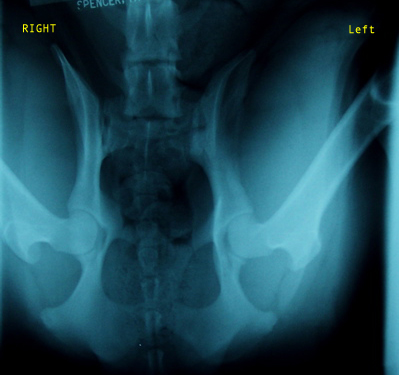

Belle PennHip Photos

Cedar Creek Belle-Aire

PennHip xray view 2